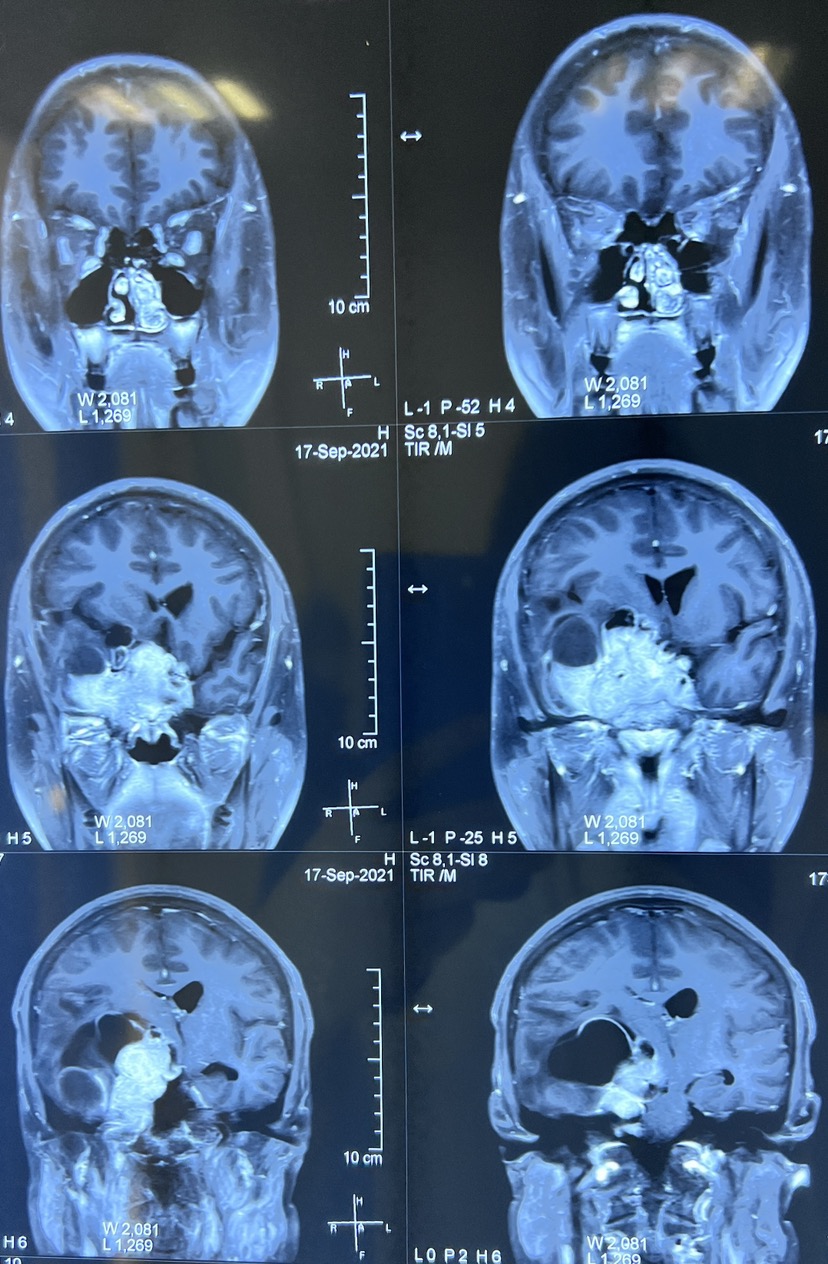

患者男性39岁以头疼视力下降,来门诊的检查。发现鞍上向脑内发展的巨大的侵袭性垂体瘤,泌乳素大于6000,根据术前的检查,该患者为泌乳素型垂体瘤,因此建议先口服溴隐亭药物治疗。

口服溴隐亭药物治疗3个月后

药物治疗后3个月复查核磁共振,发现肿瘤奇迹般的缩小,病人的一般状况也非常好。